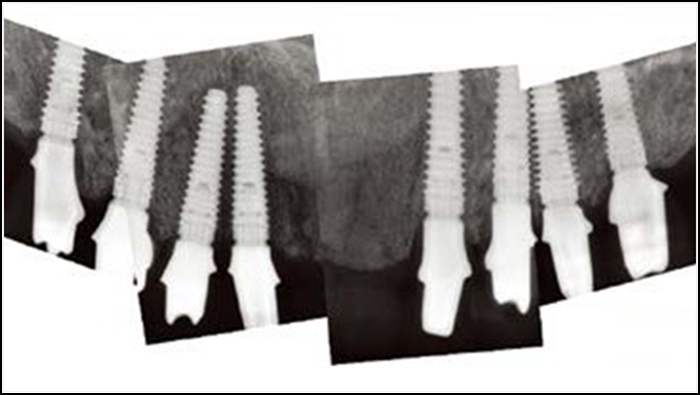

Clinical case: Advantage of fuse abutment with AnyRidge implant for immediate loading in

upper fully edentulous case

- Courtesy of Dr. Kwang Bum Park -

“AnyRidge shows excellent initial stability

& stable results after immediate loading in

upper fully edentulous case. ”